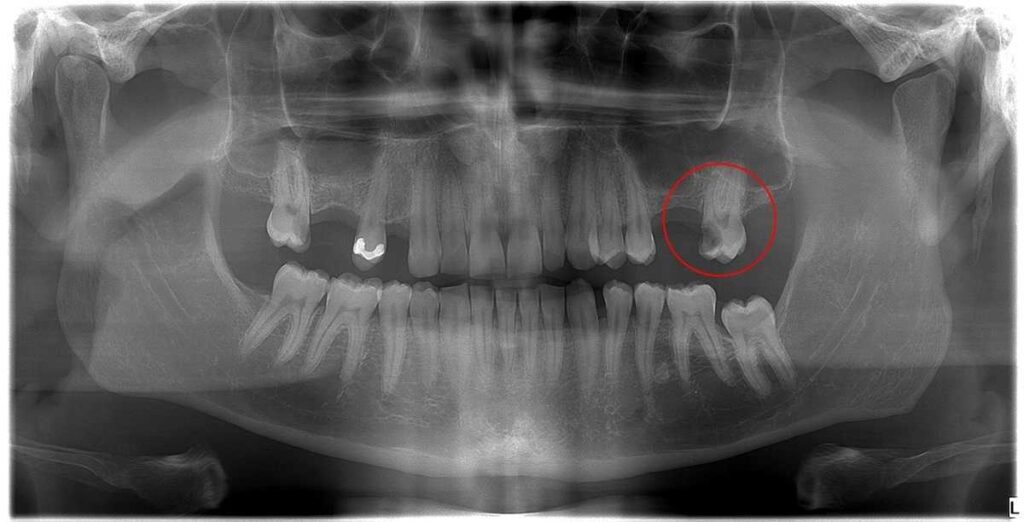

Ráadásul a mikroszkópos gyökérkezelés megjelenésével a korábban már menthetetlennek ítélt fogak jó részét is meg lehet őrizni a tulajdonosuk számára. Erről számos esettanulmányunk is tanúskodik!